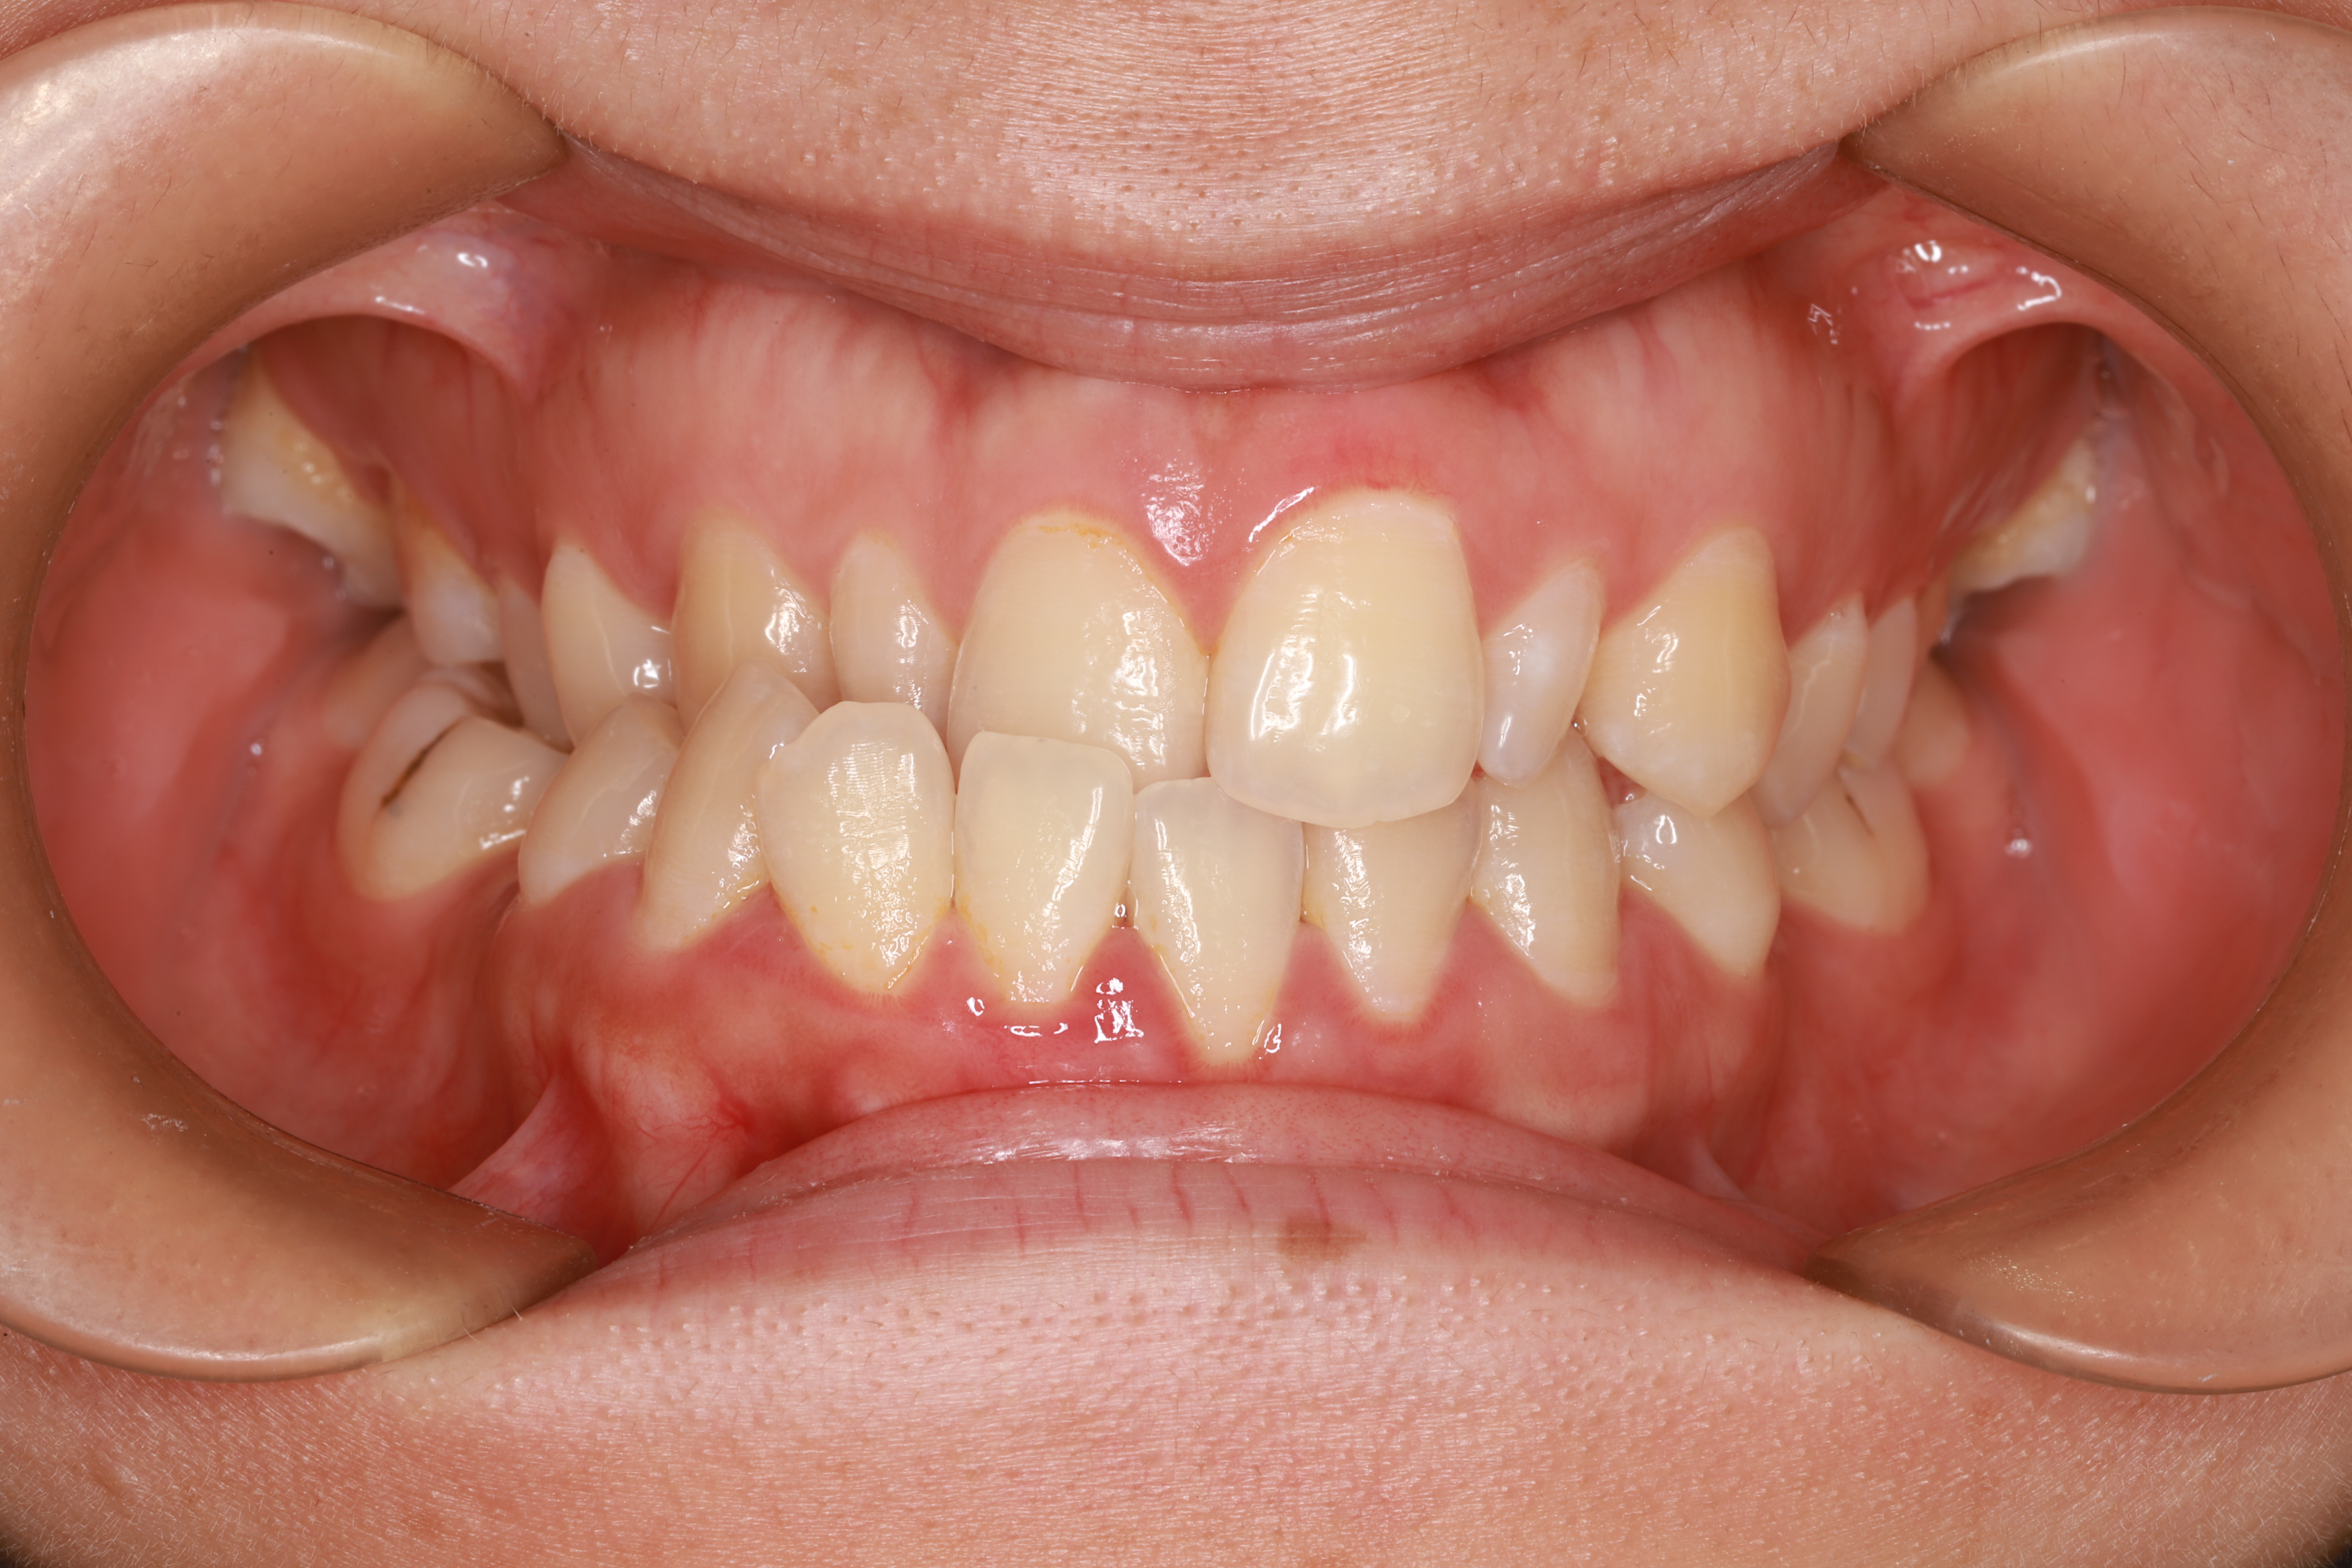

在回答这个问题之前,请看看下面几张图片。

关于儿童牙齿矫正那些事(图2)

偏颌